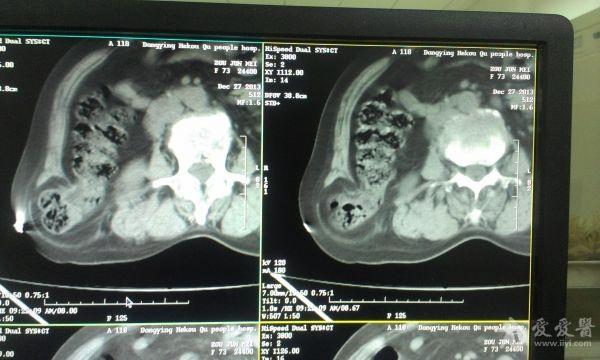

挺经典的腰疝

右腰部包块,随呼吸可运动。

非常经典的ct片,不知是继发于何种原因还是先天性的?里面内容物一般是肠管,很少发生较窄、嵌顿。